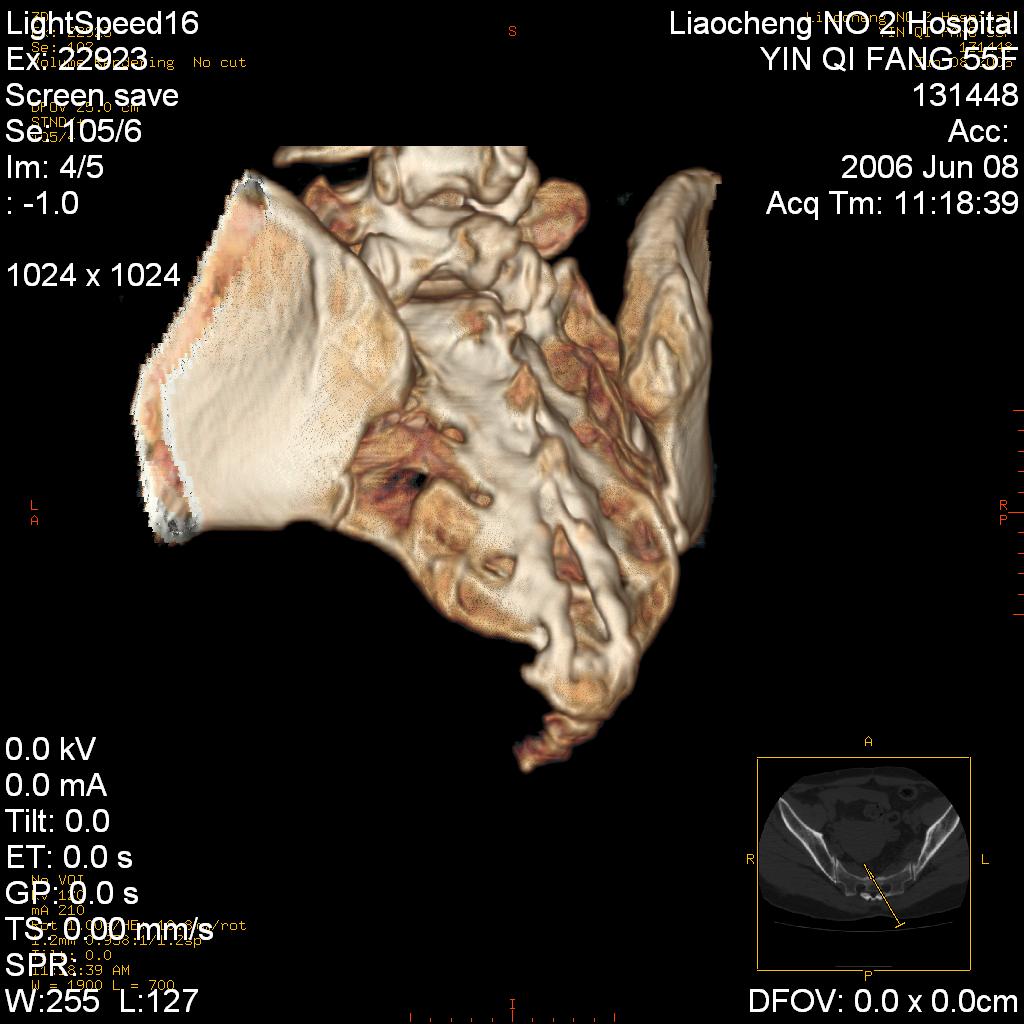

女,55岁,十余年前骶尾骨摔伤,x线平片诊断骶骨裂纹骨折,现在骶尾部又疼痛2月,x线怀疑骶骨左下部骨质破坏。大家看看,是不是先天变异。正常人不是只有4个骶孔吗?怎么此病例有5个?

两侧骶髂关节炎,确实做得很漂亮

众口一词啊,图象确实漂亮,羡煞人也!右侧骶髂关节间隙变窄,相对缘增生硬化,髂骨侧增生明显。左侧轻微类似改变,考虑双侧骶髂关节炎。余未见异常。

考虑双侧骶髂关节炎。余未见异常。

支持骶髂关节炎,3d做得很漂亮!!!!